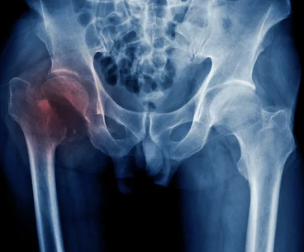

예방

- 과도한 음주 피하기

- 부신피질 호르몬 치료 시 주의

- 고관절 부위 외상 예방

- 기저 질환 관리

고관절 통증이 발생하면 정확한 진단을 위해 병원을 방문하는 것이 중요합니다.